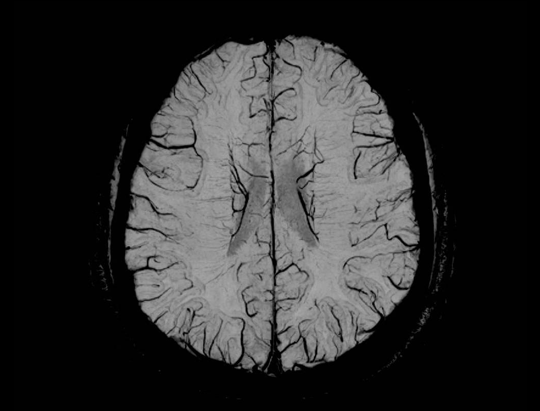

神经系统 SWI+